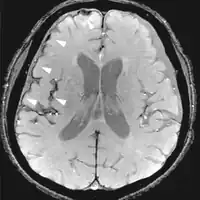

| Fluid-attenuated inversion recovery | FLAIR | Fluid suppression by setting an inversion time that nulls fluids | High signal in lacunar infarction, multiple sclerosis (MS) plaques, subarachnoid haemorrhage and meningitis (pictured).[24] | ![]() | |